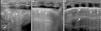

Neonato afecto de hernia diafragmática congénita izquierda que requiere tratamiento con oxigenación por membrana extracorpórea (ECMO) veno-venosa por crisis de hipertensión pulmonar. Presenta a las 48h de tratamiento en ECMO empeoramiento de parámetros respiratorios objetivándose atelectasia del pulmón izquierdo (fig. 1A) que se resuelve exitosamente mediante maniobras de reclutamiento alveolar guiadas por ecografía torácica a pie de cama del paciente (fig. 1B y C).

Ecografías torácicas del pulmón izquierdo. A) Área de consolidación que muestra pulmón hepatizado con broncograma aéreo observándose líneas hiperecogénicas paralelas a la pleura en el área consolidada (flecha) y broncograma líquido con zonas hipoecoicas en el área consolidada (asterisco), ausencia de líneas A y refuerzo pleural con derrame pleural que corresponde con patrón de atelectasia. Parámetros respiratorios VAFO: MAP 12, amplitud 40 y frecuencia 9. B) Abundantes líneas B coalescentes (asterisco), que indican abertura de atelectasia con presencia de edema pulmonar. Refuerzo de la ecogenicidad pleural y derrame pleural. Aumento de parámetros respiratorios a MAP: 15, amplitud 50 y frecuencia 8. C) Pulmón reclutado, con parénquima normal; presencia de líneas A (flecha) y escasas líneas B (asterisco). Aumento de parámetros respiratorios a MAP: 18, amplitud 55 y frecuencia 8.